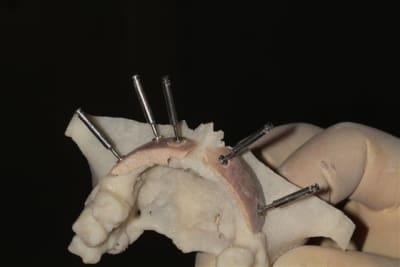

L’idée de base est d’obtenir un greffon adapté à la zone à greffer, et de donner plus de chance à la nature de faire son travail de reconstruction.

Dans un premier temps, les greffons sont préparés manuellement par votre serviteur, mais ensuite la machine outil prendra le relais, dés que seront résolus les petits problèmes d’environnement.

Une fois les greffons préparés, ils sont traités par un procédé spécifique à Biobank (CO2 supercritique) puis stérilisation (rayons gamma), et vous le verrez la pose devrait être extrêmement simplifiée.

la troisième et suivante ce sont "les greffons" définitifs.

La précision 3D du scan est elle suffisante pour une adaptation passive sur l'os réel ?

La tu nous montres sur un stereolitique obtenu à partir du scan, ok ça colle mais en bouche ?

concept très prometteur. on obtient effectivement un contact intime du greffon avec le site receveur.